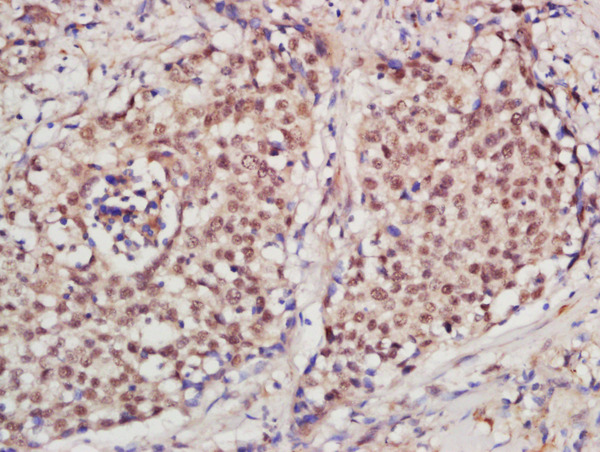

• IHC-P

IHC-P 1:200-400